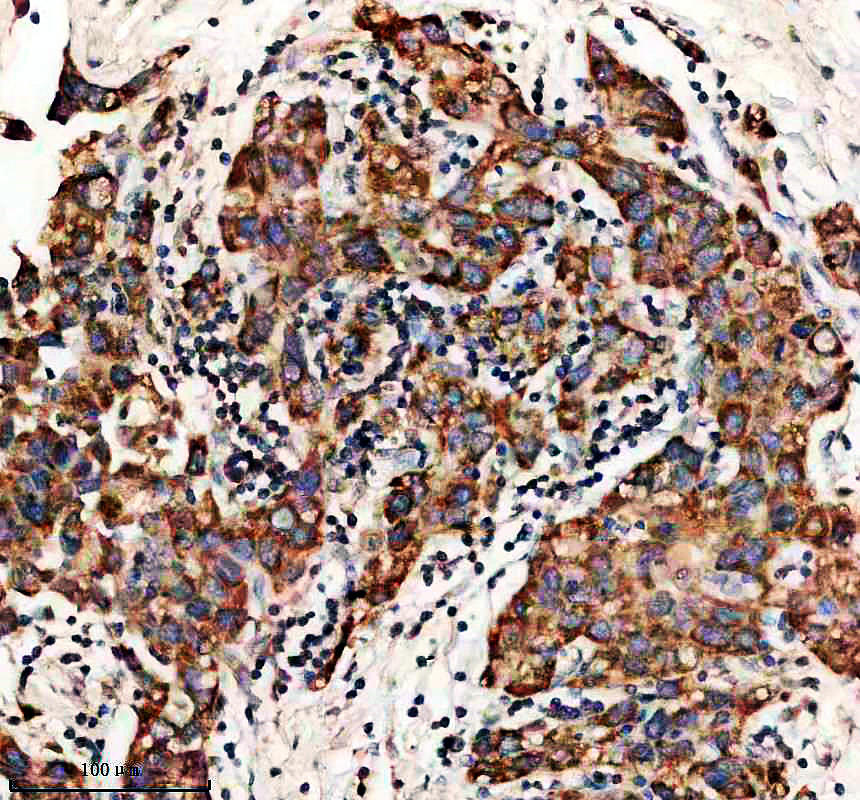

IHC analysis of ACAA1 using anti-ACAA1 antibody (A07559-4).

ACAA1 was detected in a paraffin-embedded section of human renal cancer tissue. The tissue section was incubated with rabbit anti-ACAA1 Antibody (A07559-4) at a dilution of 1:200 and developed using HRP Conjugated Rabbit IgG Super Vision Assay Kit (Catalog # SV0002) with DAB (Catalog # AR1027) as the chromogen.